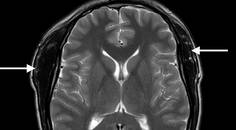

Two recent, large, phase three multicenter studies, the PREEMPT 1 and 2 trials, have shown that BoNTA is an effective treatment for adults withCM.21,22 These studies enrolled 1,384 subjects with CM in trials consisting of a 24-week, double-blind, parallel-group, placebo-controlled phase followed by a 32-week open-label phase. All subjects received at least a minimum dose of 155 units o fBoNTA administered at 31 injection sites across seven head and neck muscles using a fixed-site, fixed-dose injection paradigm and up to extra 40 units into the temporalis, occipitalis, and/or trapeziususing a modified follow-the-pain approach. (Table 2) The clinician performing the injections selected additional sites for injection based on pain location, muscle tenderness, and their personal judgment. Subjects receiving BoNTA in the doubleblindphase had statistically significant improvement from baseline after injection compared with placebo treatment in multiple clinical domains, including mean frequency of headache days and headache episodes. BoNTA-treated subjects also had fewer migraine episodes, fewer moderate or severe headache days than the placebo group. BoNTA subjects took similar amounts of acute medication but fewer triptans than controls. BoNTA treatment also significantly improved measures of disability and health-related quality of life. Based on the results of these two large randomized placebo-controls trials, the US Food and Drug Administration recently approved BoNTA for the treatment of CM.